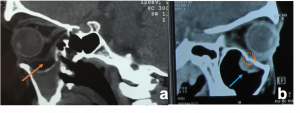

Bone remodelling may be present but no bony erosion. | Pleomorphic Adenoma. a & b). Non-contrast CT scan demonstrates well-defined, round to oval lesions, smooth in outline, associated with prominent scalloped lacrimal fossa (orange curved line) formation due to pressure without bone erosion in comparison to left orbit (orange arrows). Long-standing large tumours lobulations and radiolucent areas of cystic degeneration. |